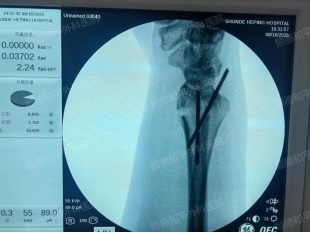

病例2:惠女士(化名),51岁,右桡骨远端闭合性骨折

摔伤后腕部疼痛、肿胀,活动受限。经检查确诊为右桡骨远端闭合性骨折,存在明显移位。

治疗方案:右腕部切开复位内固定术。手术精准复位骨折端,采用钢板螺钉固定,术后疼痛即刻缓解,功能恢复良好。